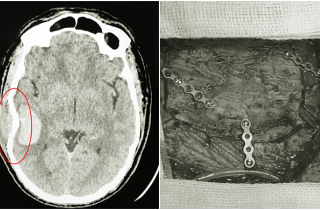

Khỏe - 18:38 - 26/04

Một nam giới 40 tuổi ở Quảng Ninh bị va chạm khi chơi bóng đá gây chấn thương sọ não, vỡ xương sọ, trong tình...

Khỏe - 08:07 - 24/04

Đang chơi bóng, bác sĩ 31 tuổi ngã xuống rồi nhanh chóng rơi vào hôn mê, ngừng tuần hoàn, kết quả chụp X-quang thấy xuất...